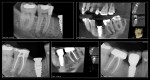

Collage-232042-Page00

This patient was in for another tooth which I will share in a following post. One year recall for #31. -Charles